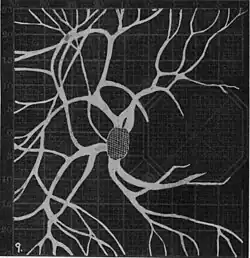

Angioscotomas were first discovered and mapped out by John Norris Evans (1891-02-28--1953-04-08)[2] in 1926, who coined the term angioscotometry to describe the painstaking charting of the scotoma of the retinal blood vessels by manual perimetry. He seated each subject in a seat in a dark setting, and tested whether they could see a tiny bright test object placed at various locations.[3] Using a 1.5 mm white disk, Evans reported intricate branch‑like scotomas that mirrored the arteries and veins emerging from the optic disc, with a full map requiring up to 2 hours to complete. He plotted this for subjects under various conditions, such as while holding breath, with glaucoma, etc. A year later, he confirmed that only short stump‑like scotomas had been noticed previously, some further data plotted with a smaller 1 mm stimuli, and under varying conditions on the subject.[4] He published a monograph on this in 1938 in which he described its use in assisting diagnosis of various conditions, such as retinal edema, glaucoma, optic neuritis, etc.[5]

20. Venous engorgement. 21. After pressure over internal 22. Same case, normal. 23. Scotoma after ligation of common carotid. 24. Edematous swelling of nerve and retina. 25, Normal blind spot of other eye. -